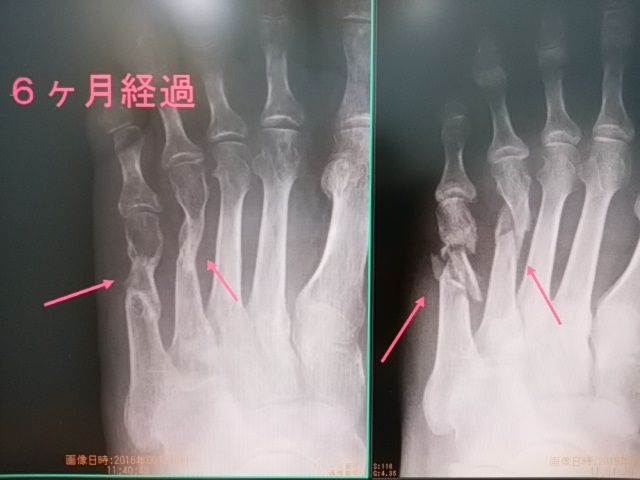

今回、鎖骨骨折後 1か月弱 にもかかわらず 第3戦 イギリス GP に出場。

帰国後 すぐにレントゲンです!

骨癒合前の 出場でしたが 今回の転倒でも 問題ありませんでした